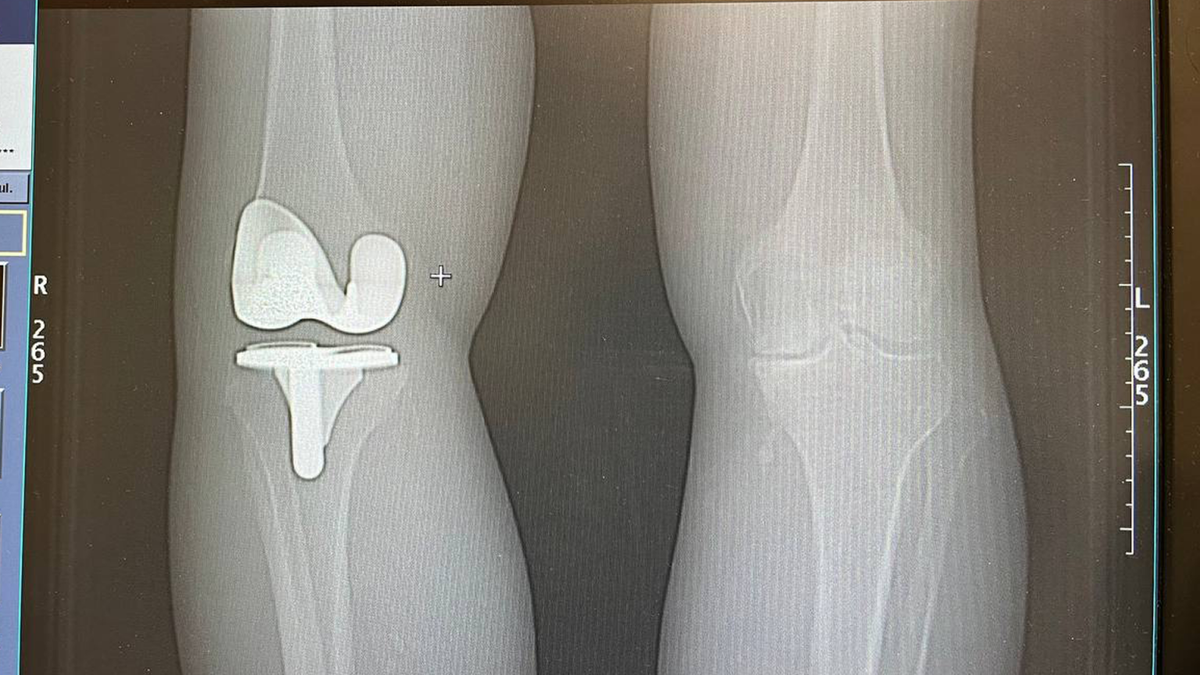

Диагностика: когда решение становится очевидным

После очной консультации и анализа снимков (рентген, МРТ) стало ясно:

речь идёт о

прогрессирующем артрозе коленного сустава.

Почему был выбран эндопротез MicroPort Medial-Pivot

Для операции мы выбрали систему MicroPort Medial-Pivot (MP) — один из самых физиологических вариантов эндопротезирования коленного сустава.

MicroPort Medial-Pivot работает по механизму

«Ball-in-Socket» («шар во впадине»).